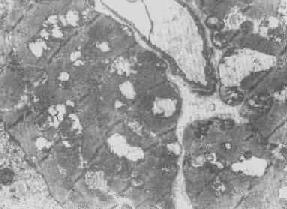

肾小管上皮细胞线粒体部分空泡变

图1-10肾小管上皮细胞线粒体部分空泡变

线粒体肿胀(基质型)空泡变(心肌缺氧)

图1-11 线粒体肿胀(基质型)空泡变(心肌缺氧)